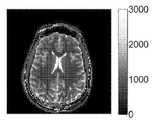

도 12a-12d는, 핵 자기 공명(NMR) 핑거프린팅과 연관된 예시적인 인 비보(in vivo) 결과들을 도시한다. 도 12a는 T1 맵(ms)을 도시하고, 도 12b는 T2 맵(ms)을 도시하고, 도 12c는 오프-공명 맵(Hz)을 도시하며, 도 12d는 양성자 밀도 맵을 도시한다.

Figures 12A-12D illustrate exemplary in-vivo results associated with nuclear magnetic resonance (NMR) fingerprinting. FIG. 12A shows a T1 map (ms), FIG. 12B shows a T2 map (ms), FIG. 12C shows an off-resonance map (Hz) and FIG. 12D shows a proton density map.

도 12a-12d는 다른 NMR 핑거프린팅 실험과 연관된 인 비보 결과들을 도시한다. 도 12a는 T1 맵(ms)을 도시하고, 도 12b는 T2 맵(ms)을 도시하고, 도 12c는 오프-공명 맵(Hz)을 도시하며, 도 12d는 양성자 밀도 맵을 도시한다. 도면들 12a-12d를 생성하기 위한 정보는 일 예시적인 MRF 접근법을 사용하여 동시에 포착되었다.Figures 12A-12D show in-vivo results associated with different NMR fingerprinting experiments. FIG. 12A shows a T1 map (ms), FIG. 12B shows a T2 map (ms), FIG. 12C shows an off-resonance map (Hz) and FIG. 12D shows a proton density map. The information for generating the figures 12a-12d was simultaneously captured using an exemplary MRF approach.